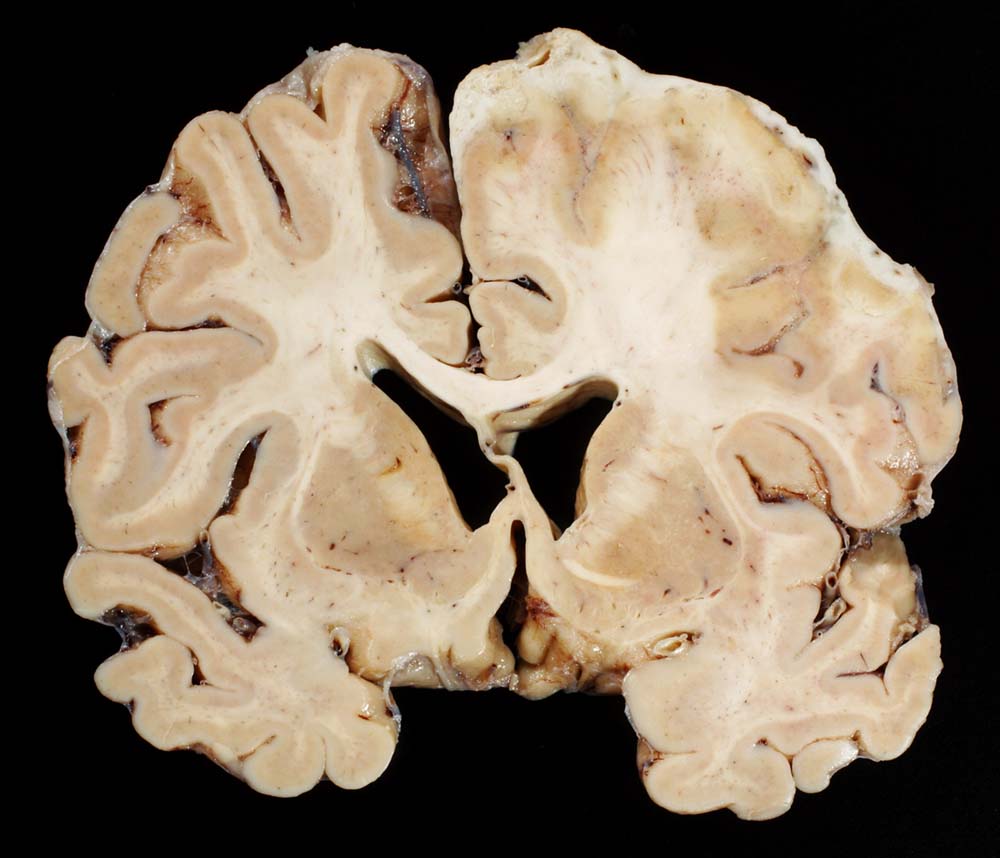

Morphologie:

Der makroskopische Befund bei bakterieller Meningitis kann sehr diskret sein. Die meningealen Gefässe sind hyperämisch und die Hirnoberfläche wird von einem grüngelben Eiterbelag bedeckt (eher basal bei Hämophilus influenzae, eher über der Konvexität bei Pneumokokken=Haubenmeningitis). Histologisch ist der Subarachnoidalraum mit Eiter gefüllt. Bei weniger schweren Fällen finden sich die neutrophilen Granulozyten bevorzugt um die leptomeningealen Gefässe.